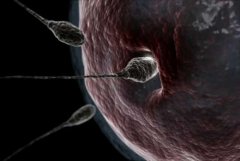

为什么中老年人容易患慢性脑供血不足呢?大家都知道,大脑是人体的重要器官,耗氧量相对较大,大脑的重量大约只占身体重量的2%,但是耗氧量却占全身好氧量的20%。大脑所需的氧全部由血液供给,所以必须有足够的血液供应大脑才能正常活动。衡量大脑血液供应的标准是脑血流量,脑血流量一旦减少,脑细胞的供氧供能也随即减少;脑组织只要缺血10余秒钟,就会引起大脑的功能发生变化。如果大脑某一部分血流在较短时间内完全阻断,会发生局部脑组织坏死,这就是脑梗塞;如果大脑供血不是完全阻断而是慢慢地减少,这就是慢性脑供血不足。随着年龄的增长,大脑的血液供应会逐渐减少。儿童时期脑血流量大约为 100毫升(100毫升/100克脑组织·分),成人为50毫升(50毫升/100克脑组织·分),而健康老人只有35毫升(35毫升/100克脑组织· 分);再加上中老年人的脑组织对缺血的耐受性相对较低,脑血管的自动调节机能也逐渐下降,因此只要供血发生轻微的变化,就会明显影响脑血流量,从而导致慢性脑供血不足的发生。